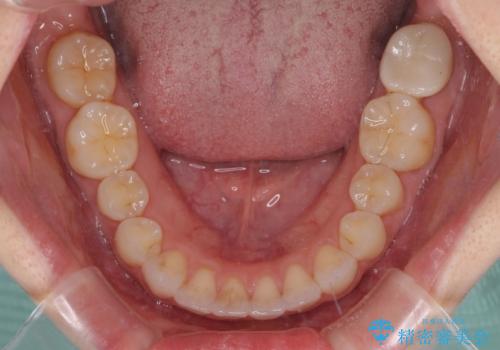

- 矯正治療の後戻りを気にして来院された患者様です。

後戻りは軽微でしたが、舌突出癖が認められ、初診時には上下前歯に舌がはまるスペースができていました。

舌突出癖の改善を行いながら、インビザライン・ライトにより矯正治療を行うこととしました。

舌突出癖の改善により上下前歯が接触するようになり、前歯でものを咬みきる必要のある食事がスムーズに行えるようになりました。